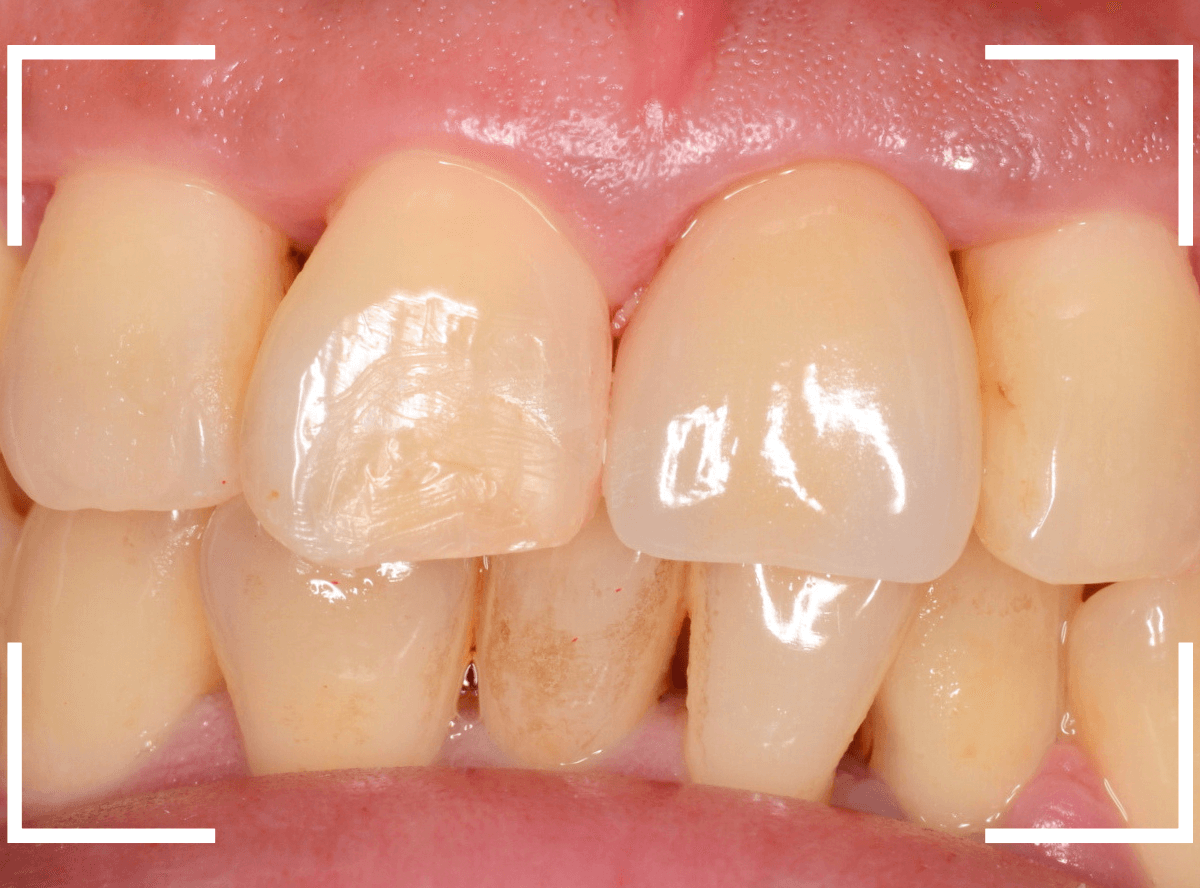

set前との比較です。

治療前と治療後の比較、前から見たところです。